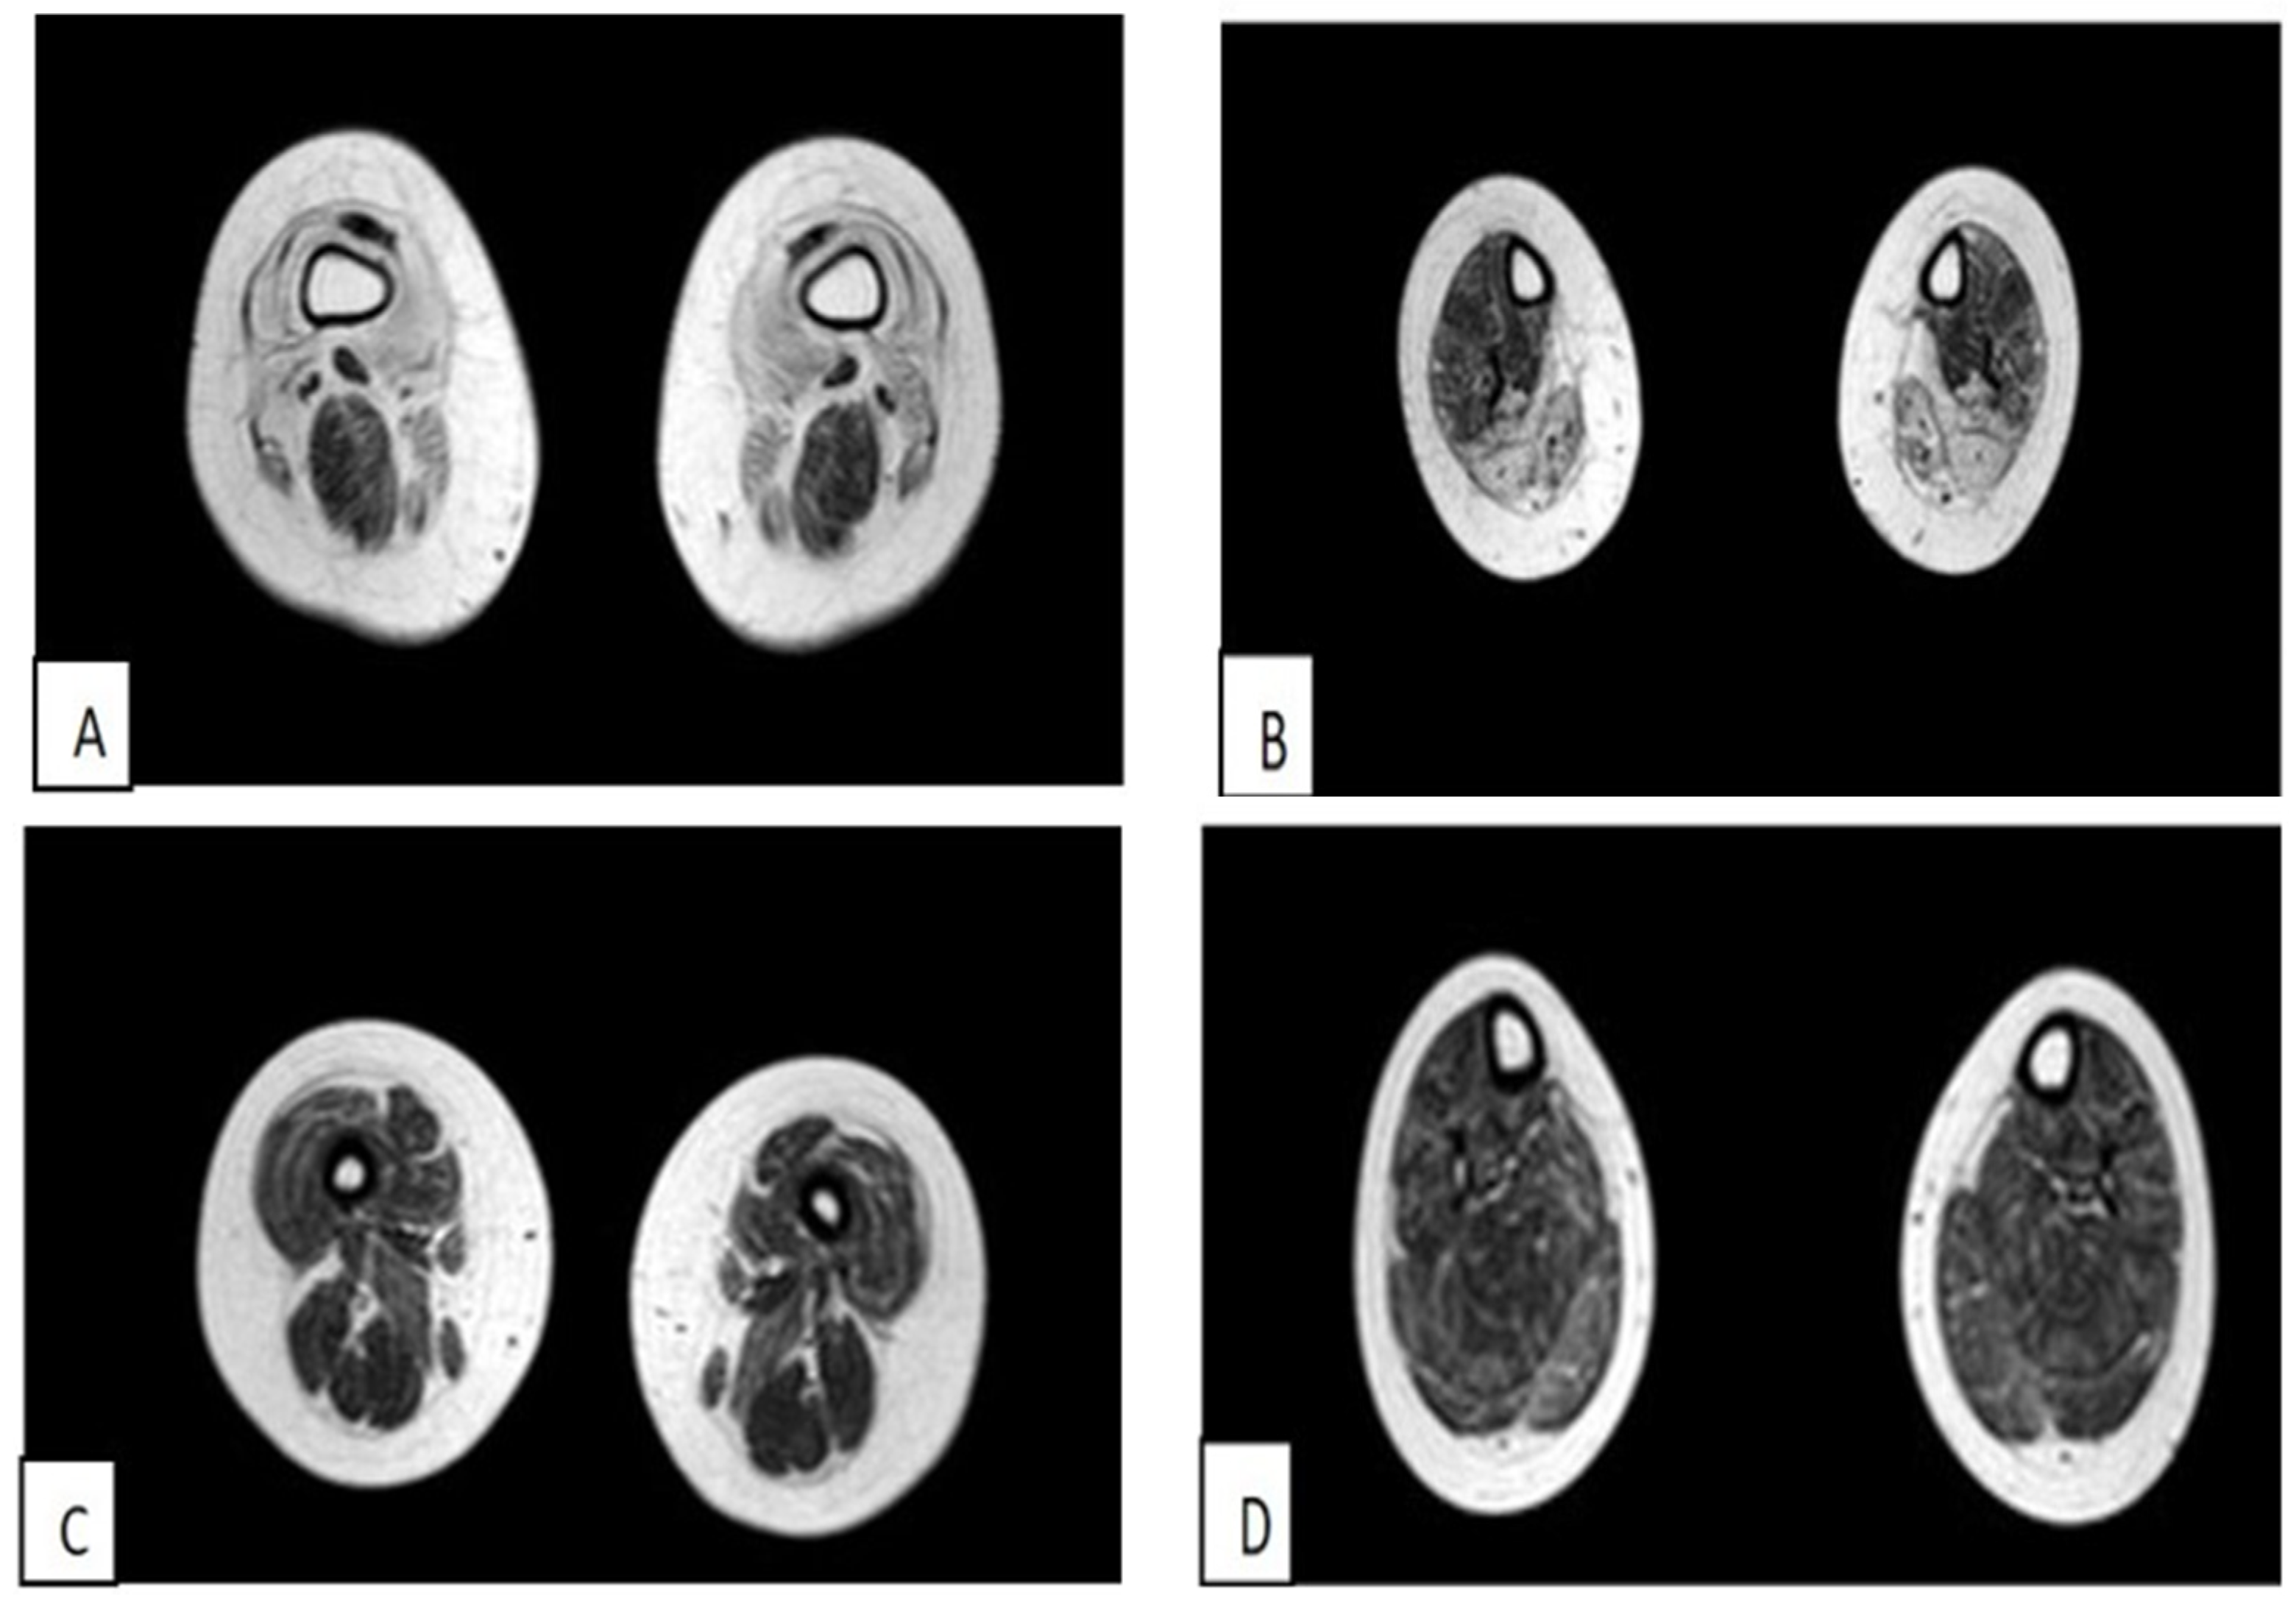

3.1.1. The First Case of Family 1 (Patient 1)

3.1.2. Second Case of Family 1 (Patient 2)

3.1.3. First Clinical Case of Family 2 (Patient 3)

3.1.4. Second Case of Family 2 (Patient 4)

3.1.5. Third Case of Italo-Spanish Family (Patient 5)

3.1.6. Fourth Case of Italo-Spanish Family (Patient 6)